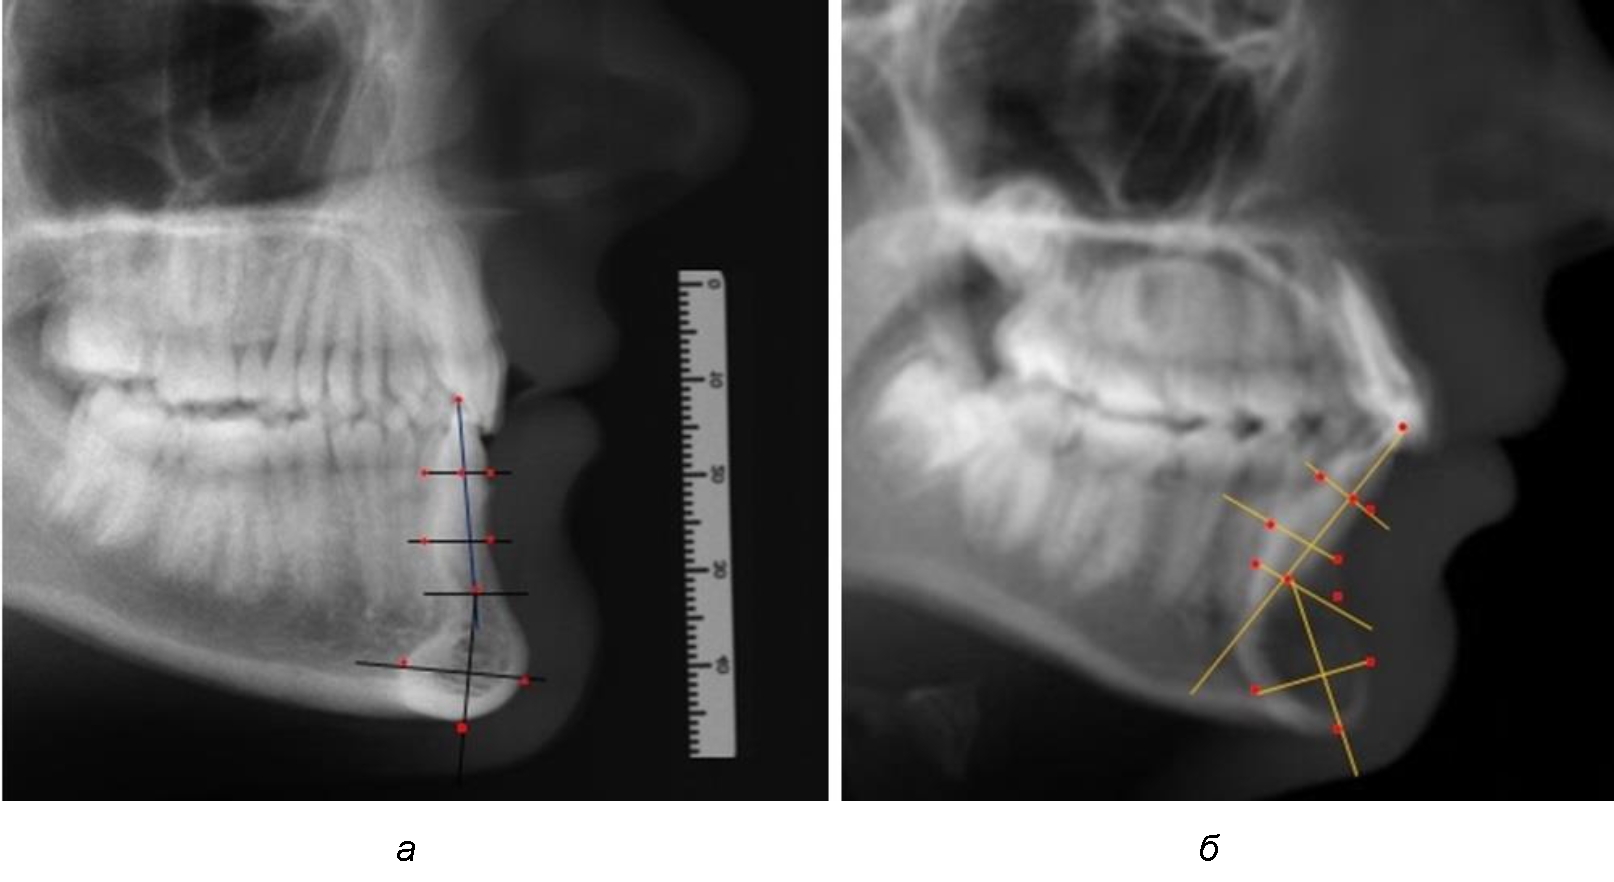

Предложен метод исследования зубочелюстных сегментов, который проводился на масштабированных фотографиях, и в программе Microsoft PowerPoint обозначались точки с последующим построением линий, необходимых для измерения по вертикали и сагиттали.

На режущем крае нижнечелюстного резцового сегмента устанавливалась точка, обозначаемая как IsL.

Определяли положение цервикальных точек резцов на вестибулярной и лингвальной поверхностях, которые соединяли цервикальной линией. Условная срединную вертикаль зуба соединяла резцовую точку IsL с серединой цервикальной линии и, как правило, доходила до апикальной точки, которую обозначали как Ap. Линия IsL–Ap определяла высоту зубоальвеолярной части резцового нижнечелюстного сегмента. Определяли высоту коронки и корня зуба. Кроме того, на вестибулярной поверхности зубочелюстного сегмента отмечали точку наибольшей вогнутости альвеолярной части, которая обозначалась как супраментальная точка Downs (Bsm). Измерялось расстояние IsL–Bsm, которое служило для определения проекции супраментальной точки Downs на язычную поверхность сегмента и обозначалась как точка Bsm'.

Проекцию верхушки корня резца на кость обозначалась как точка B нижнего апикального базиса по Schwarz. Соединяли апикальную точку с точкой нижнечелюстного апикального базиса линией, которая доходила до язычной поверхности подбородочного выступа и определяла положение точки B'. Таким образом, в зубоальвеолярной части сегмента выделялись две зоны: верхняя и нижняя, с последующим измерением по вертикали. При этом, как правило, верхняя зона была представлена компактной костной тканью, а в нижней зоне определялось наличие губчатой ткани между компактной пластинкой и стенкой альвеолы.

При анализе боковых телерентгенограмм использовали фрагменты гнатической части, на которых оценивали вертикальные и сагиттальные параметры резцового нижнечелюстного сегмента, на который наносили те же ориентиры, что и при анализе нативных препаратов и их рентгенограмм.

При необходимости и/или возможности проведения КЛКТ-исследования проводили анализ с сопоставлением фрагмента, что повышало точность диагностических мероприятий (рис. 2).

Рис. 2. Фрагменты ТРГ с ориентирами для измерения параметров резцового сегмента (а) и с наложением фрагмента КЛКТ (б)

Линейные и относительные показатели, полученные при исследовании нативных препаратов, могут быть использованы в ходе сравнительного анализа с данными результатов ТРГ. Результаты исследования ТРГ людей с физиологической окклюзией показали, что встречаются различные варианты нижнечелюстного сегмента, которые определяются вертикальными и сагиттальными параметрами, представленными в табл. 2.

Обращает на себя внимание то, что по большинству параметров не отмечено достоверных различий с показателями, полученными при измерении нативных препаратов зубочелюстных сегментов.

Отношение размеров корня к коронки нижнего резца, которое в среднем по группе составляло 1,53 ± 0,04, при сигмальном отклонении 0,11.

Отношение высоты зубоальвеолярного сегмента к высоте подбородочного выступа составляло 1,21 ± 0,04 (ϭ = 0,13).

Так же, как и при исследовании сегментов, обращает на себя внимание факт того, что из вертикальных параметров зубоальвеолярной части сегмента наиболее вариабельным является размер между апикальными точками Downs и Schwarz (BSM–B), который составлял (6,79 ± 0,41) мм, при величине сигмального отклонения 1,78.

Также большая ошибка репрезентативности и сигмальное отклонение было отмечено при оценке ширины подбородочного выступа.

Варианты резцовых сегментов нижней челюсти различные как по ширине, так и по высоте, а также по расхождению положения апикальных точек по Downs и Schwarz представлены на рис. 4.

Рис. 4. Особенности нижнечелюстного резцового сегмента на ТРГ у людей при среднем (а), широком (б) и узком (в) вариантах